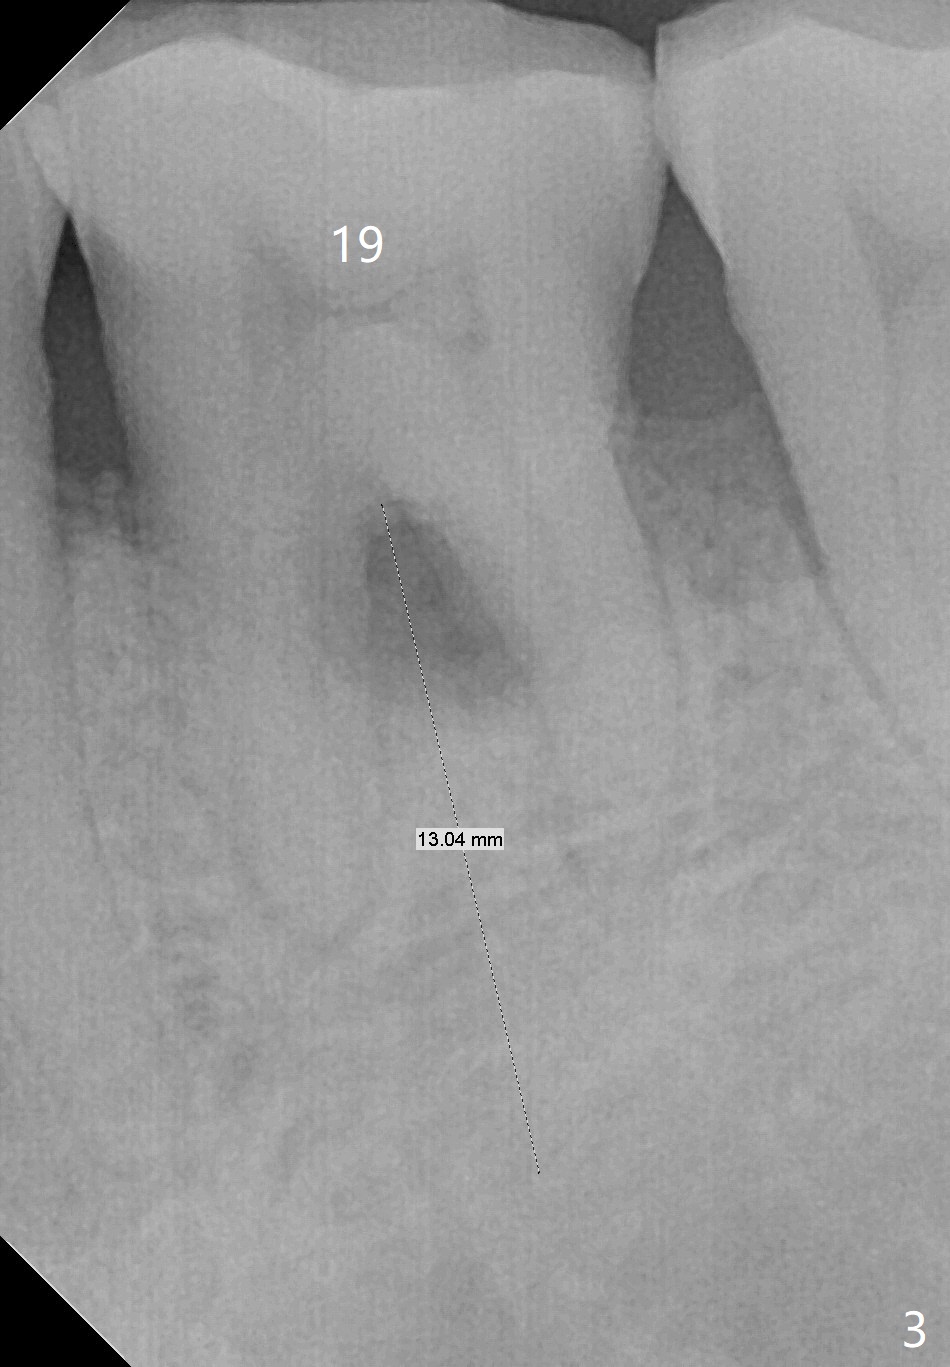

Improve Implant/Crown Ratio and Prevent Periimplantitis

A 59-year-old man seems to have perio-endo disease at #19 (Fig.1-3). To improve implant/crown ratio, place IS implant at the crestal level (not too deep). To prevent periimplantitis (buccal plate postop resorption), place the implant lingually. Prepare surgical handpiece to initiate osteotomy or to flatten the septum.